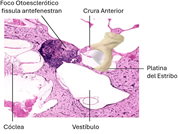

Figura 1. Foco otoesclerótico |

La otosclerosis es una enfermedad que afecta la cápsula ótica, caracterizada por una remodelación ósea anormal. Este proceso de remodelación, que ocurre de manera natural en todos los huesos del cuerpo, implica un delicado equilibrio entre la resorción ósea mediada por los osteoclastos y la formación ósea realizada por los osteoblastos. En la otosclerosis, esta alteración a menudo resulta en una fijación parcial del estribo, particularmente en la porción anterior de la ventana oval, específicamente en la fissula antefenestran (ver Fig. 1).